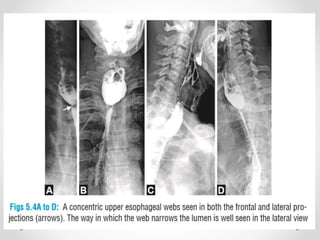

Pharyneageal web

Pharyneageal web Classical findingin carcinoma –rat tail appearance.